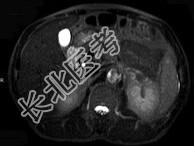

- 单项选择题男,52岁, 下肢无力伴多饮多尿2年余,实验室检查: 低血钾,血醛固酮水平及24小时尿醛固酮定量超过正常值, MRI检查如图所示,应诊断为 ( )

A、左肾上腺囊肿

B、左肾上腺腺瘤

C、左肾上腺嗜铬细胞瘤

D、左肾上腺髓脂瘤

E、左肾上腺转移瘤